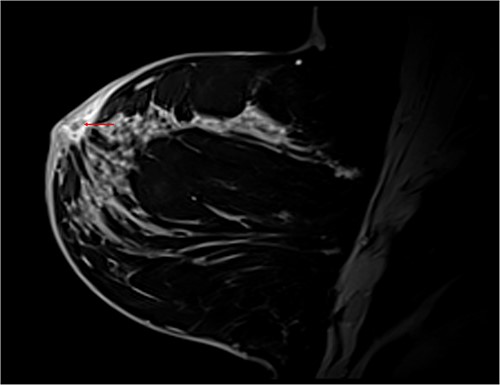

Differential diagnoses included granulomatous mastitis (GM) and inflammatory breast cancer (iPrevent score of 11.2% lifetime risk) [1]. A complete triple assessment was performed with bilateral breast imaging and core biopsy of the retroareolar lesion. Magnetic resonance imaging demonstrated benign breast changes and histopathology demonstrated suppurative chronic inflammation with granulation tissue and adjacent fibrosis without evidence of granulomas or malignancy (Fig. 4). Doxycycline was commenced with significant clinical improvement, supporting an HS diagnosis. The patient was discharged with ongoing multidisciplinary management involving a breast surgeon, an infectious diseases physician and a dermatologist.

T1 Dixon sagittal MRI of the breast—changes restricted to the skin. Diffuse skin thickening of the periareolar region with small fluid collections (red arrow).